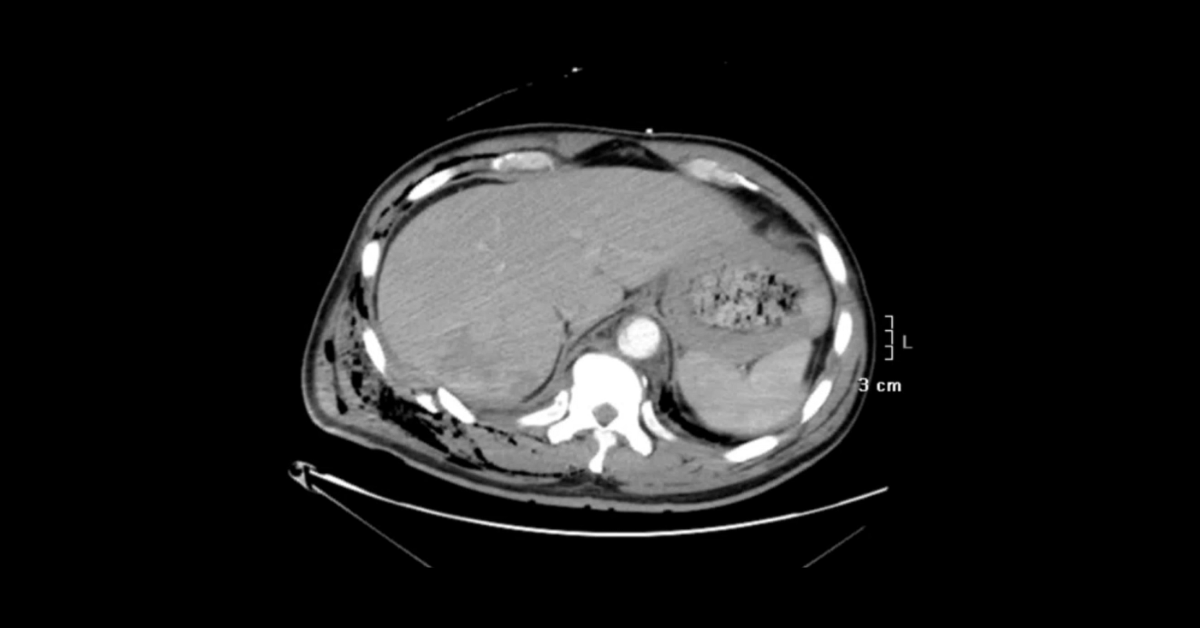

A collection of thoracic CT cases demonstrating a variety of thoracic injuries.

1. Learn the importance of aortic evaluation in trauma imaging.

2. Understand the implications of microembolic phenomena in the solid abdominal organs in cases of thoracic trauma.

3. Learn the different anatomic gas collections associated with bronchial injuries.